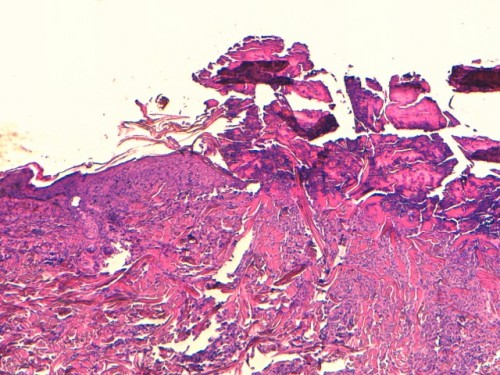

L’histologie décrit une dermatose kératoséborrhéique péri-vasculaire superficielle associée à des lésions surinfectées sévères (photos 4 et 5). L’épiderme présente des ulcérations multifocales, et est remplacé par endroit par un magma nécrotique. De nombreux amas bactériens cocciformes sont visibles. Le derme présente un œdème et un infiltrat inflammatoire péri-vasculaire riche en mastocytes et éosinophiles et une congestion vasculaire. Aucune image microscopique directement imputable à l’infection par le FIV n’a pu être mise en évidence.

Photo 4 : (HE*40), lésions pyotraumatiques multifocales de l’épiderme, épaisses croûtes avec amas bactériens bleutés

Photo 5 : (HE*400), interface épiderme-derme avec infiltrat de mastocytes, neutrophiles et éosinophiles